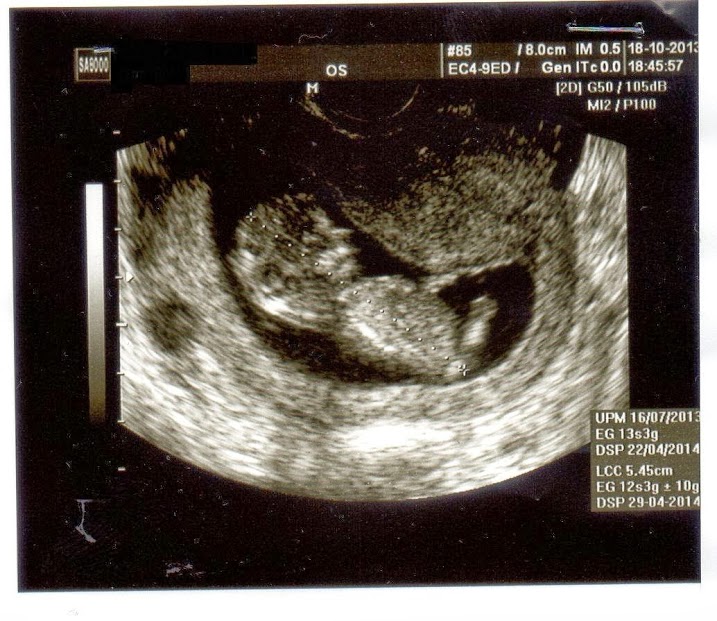

I am 12 weeks + 5 day pregnant...this is my first baby...

Any guesses on my baby's gender using the skull shape theory?

So what gender do you think my baby could be ?????boy o girl?

I will go with boy, but I am horrible at the skull theory, lol.

The skull looks more boy to me.